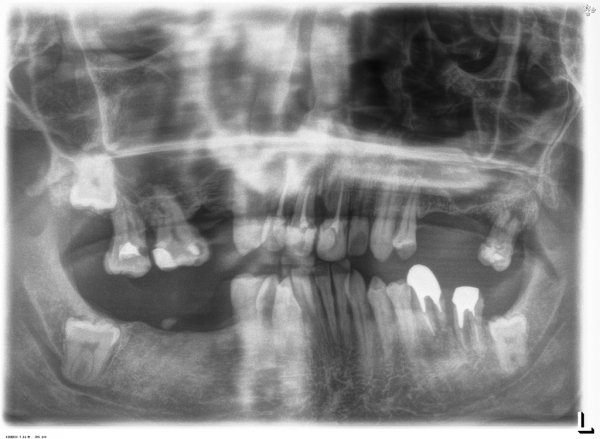

У моего знакомого по тем или иным причинам выпали зубы, и их всего осталось двенадцать. И по этому поводу у меня несколько вопросов.

Сколько примерно будет стоить вставить зубы, приблизительно хотя бы? Просто сколько я ни смотрел на расценки на различных сайтах, не пойму, как и из чего складывается цена на зуб или на зубы в целом. Будет ли дешевле вставить несколько зубов сразу, чем по отдельности через какой-то период времени?

Мы сейчас с вами ведем переписку слегка абстрактную, так как ни я, ни вы не знаем точную информацию и диагноз. Что вы имеете в виду под словом "вставить": имплантацию либо мостовидное протезирование"? Для имплантации необходимо планирование, исследование костной ткани и еще куча факторов. Для протезирования мостовидными протезами также, необходимо понимать картину и возможность данного метода. Хочу также ответить, что невозможного ничего нет, все зависит от ваших желаний, показаний и, естественно, финансовых возможностей.